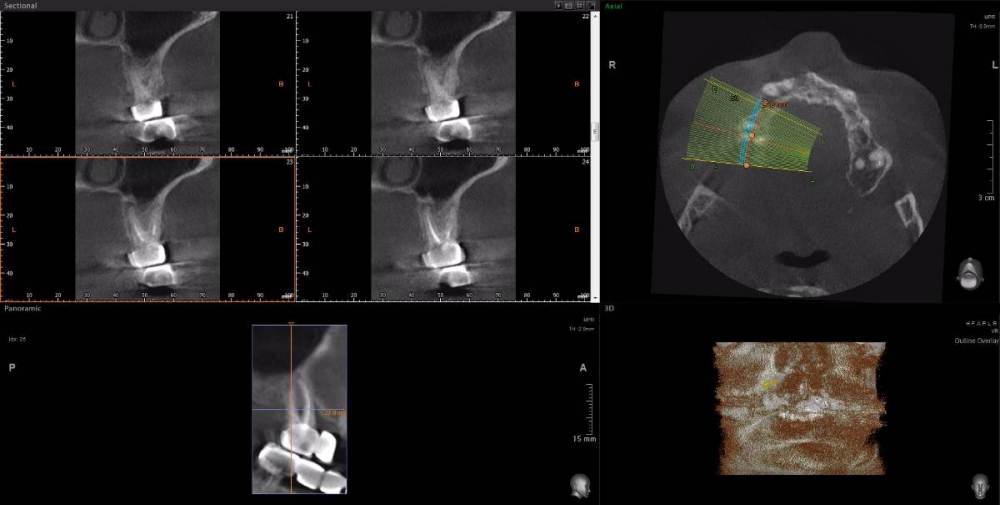

Dude Опубликовано 1 апреля, 2021 Автор Поделиться Опубликовано 1 апреля, 2021 https://disk.yandex.ru/d/6d0pmZ1zArn1Og Так? Ссылка на комментарий